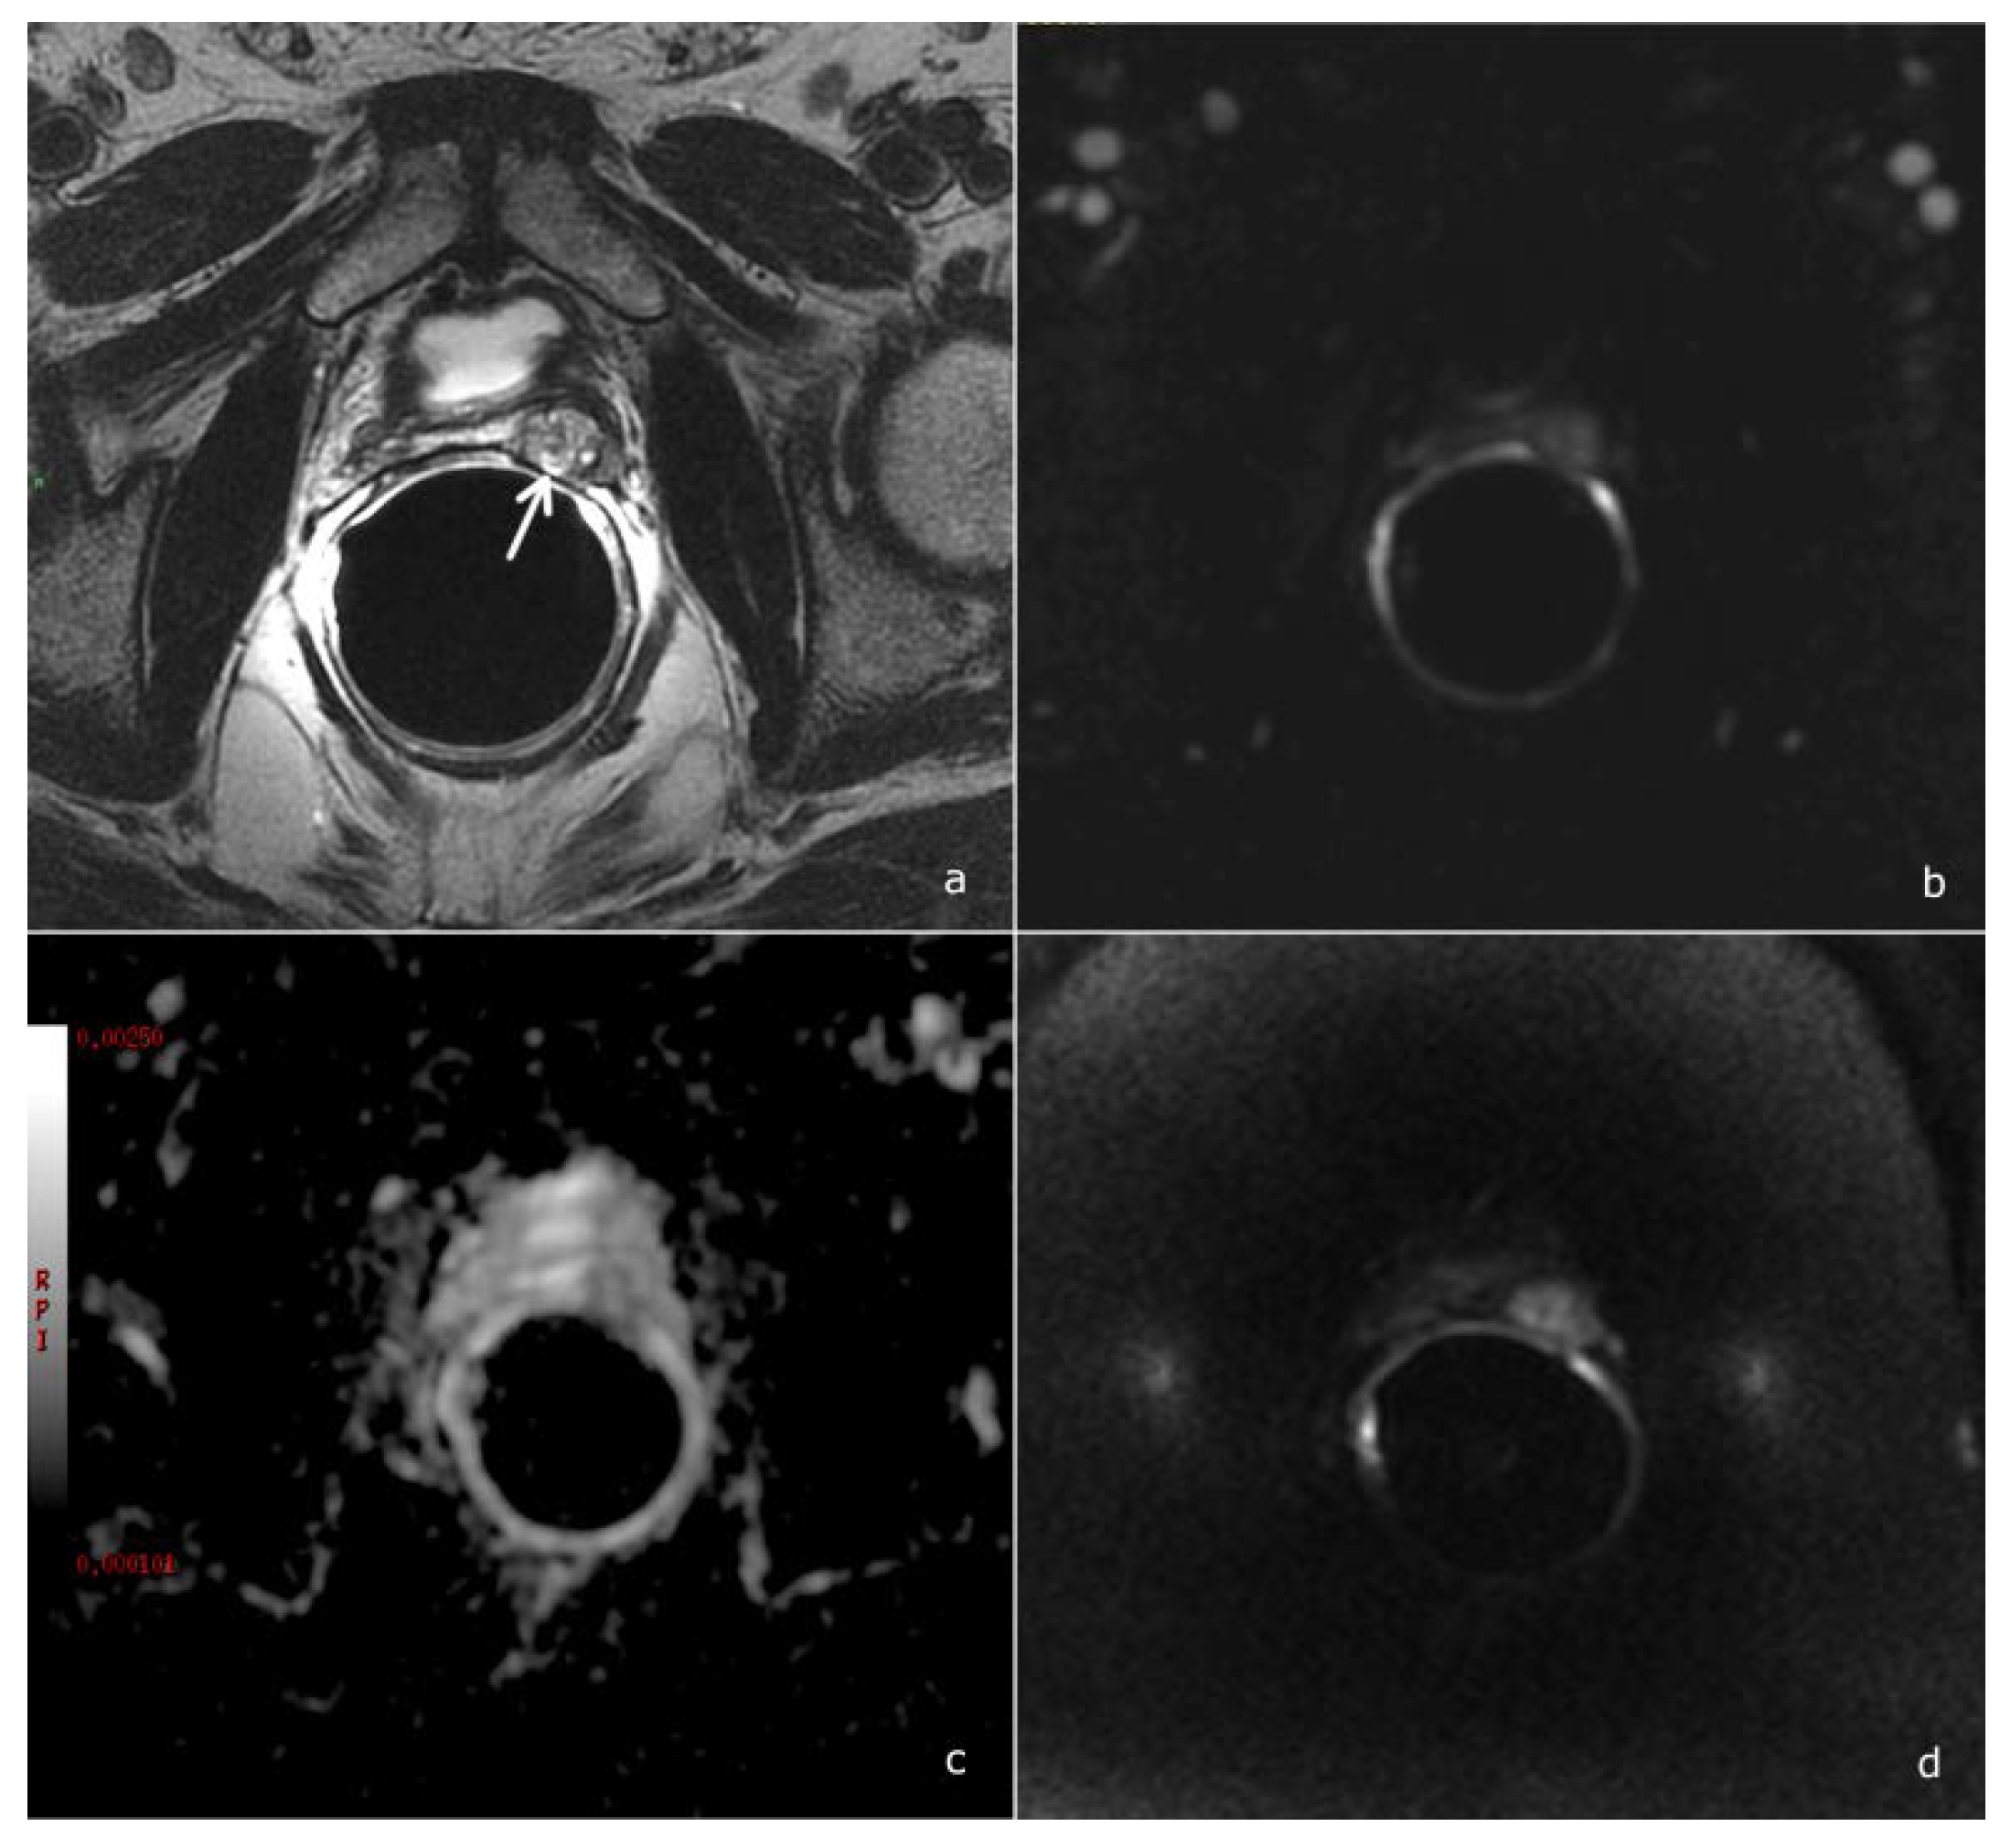

- Diffusion-weighted imaging (DWI): a single-shot echo-planar sequence with a high b-value (2000 s/mm2) and another single-shot echo-planar sequence with two different b-values (50 and 1000 s/mm2), this latter for the calculation of the apparent diffusion coefficient (ADC) map.

- DCE acquisition: three-dimensional (3D) T1-weighted Time-of-Flight Spoiled Gradient-Recalled sequence on the axial plane during the intravenous injection of a gadolinium-based contrast agent at a flow rate of 3 mL/sec followed by 15 mL of saline solution. The 3D data sets were acquired with a 10 s temporal resolution; the acquisitions before the contrast agent administration were analyzed to detect foci of hemorrhage.

- Gaudiano, C.; Ciccarese, F.; Bianchi, L.; Corcioni, B.; De Cinque, A.; Giunchi, F.; Schiavina, R.; Fiorentino, M.; Brunocilla, E.; Golfieri, R. The role of MRI in the detection of local recurrence: Added value of multiparametric approach and Signal Inten-sity/Time Curve analysis. Arch. Ital. Urol. Androl. 2022, 94, 25–31. [Google Scholar] [CrossRef]